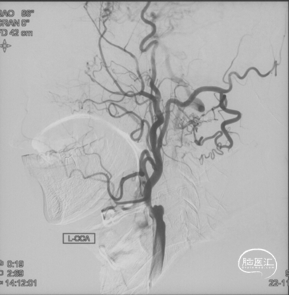

CTA和DSA

CTA和DSA所见:双侧颈内动脉闭塞,右侧椎动脉发出PICA后闭塞,左侧椎动脉V1-V2段闭塞。两条健壮的侧枝通过肌支吻合汇入左椎动脉V2段,构成了整个大脑大部分供血的主要来源。双侧颈外动脉亦有少量血流供应颅内。这样的颅内供血很容易发生失代偿,导致TIA甚至脑梗。